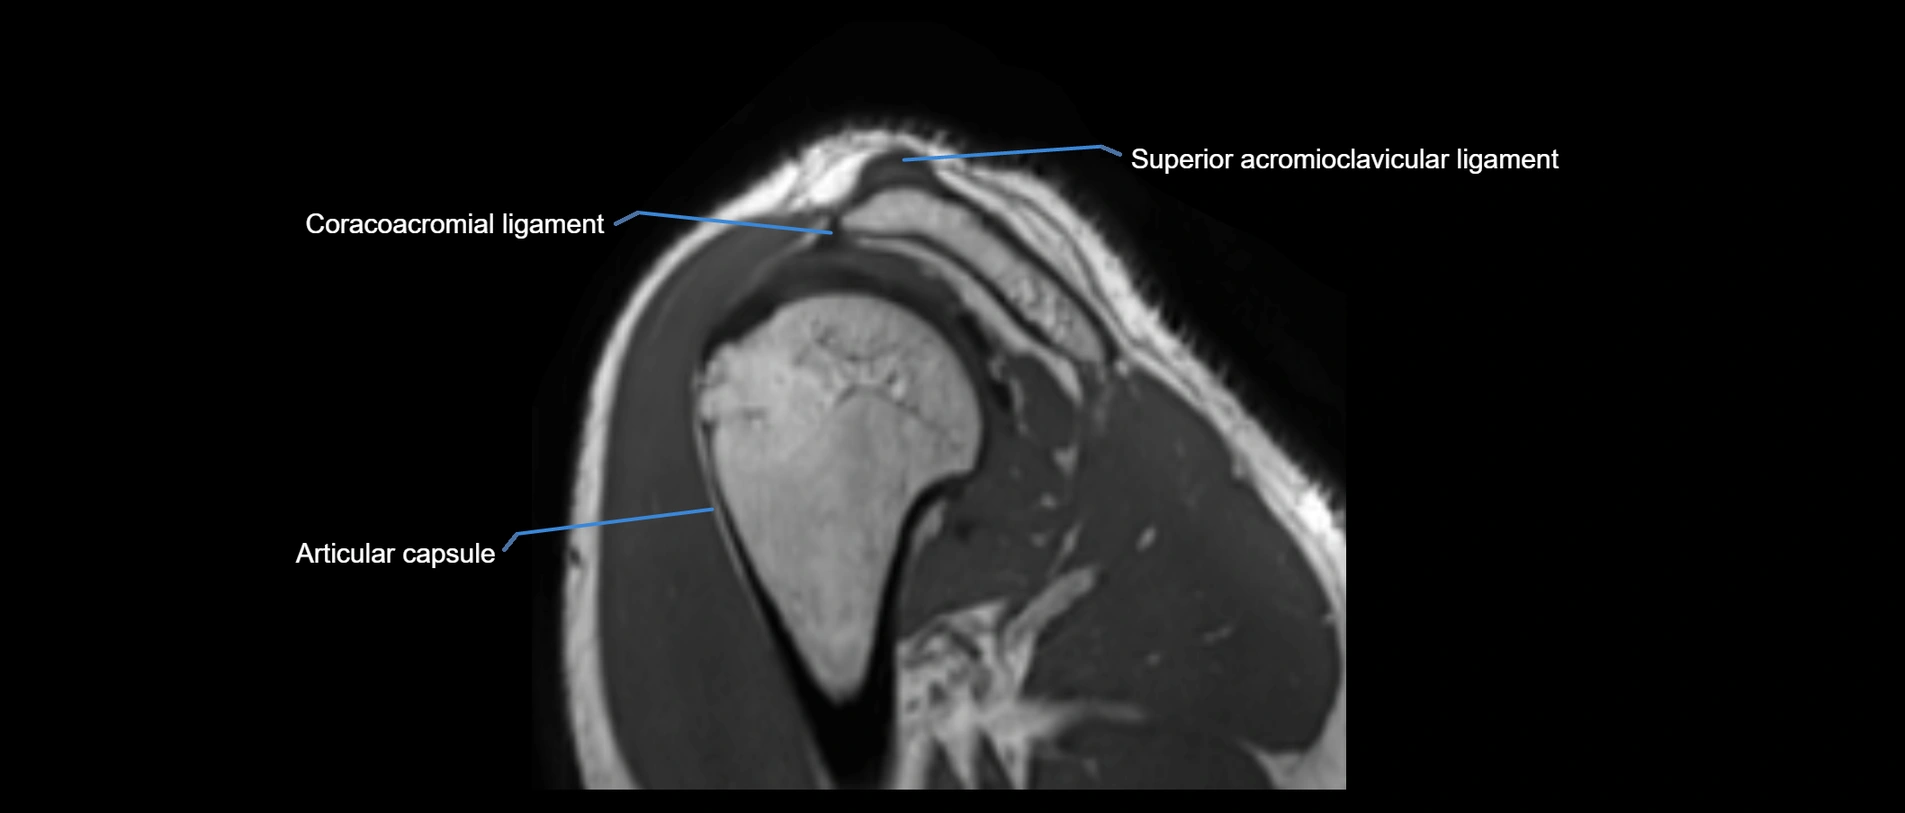

MRI images

image

MRI Appearance

• T1-weighted images:

• Normal ligament: Low signal (dark linear band) spanning acromion to clavicle.

• Surrounding fat planes: Bright, delineating the ligament clearly.

• Marrow of clavicle and acromion: Bright due to fatty content.

• Tears: Discontinuity or irregular thickening with intermediate-to-bright signal.

• Chronic injury: Thinning, fraying, or irregular low-signal fibers with adjacent scarring.

• T2-weighted images:

• Normal ligament: Low signal, homogeneous.

• Partial tear or sprain: Focal hyperintensity or thickening.

• Complete tear: Discontinuity with fluid-bright gap between clavicle and acromion.

• Associated edema: Bright signal in distal clavicle or acromion marrow.

• STIR:

• Normal ligament: Dark linear band.

• Injury or inflammation: Bright hyperintense signal in and around ligament fibers.

• Highlights periligamentous soft-tissue edema, especially in acute trauma.

• Proton Density Fat-Saturated (PD FS):

• Normal ligament: Low signal, uniform thickness.

• Partial tear or sprain: Bright signal or contour irregularity.

• Complete tear: Clear discontinuity with bright signal gap and joint effusion.

• Excellent for assessing joint capsule, coracoclavicular ligaments, and periarticular edema.